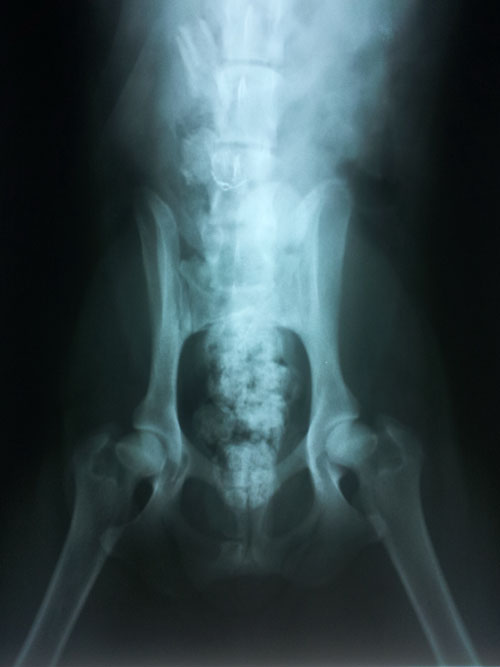

Donmoon Baron Brave Heart

ข้อสะโพก - ปกติ HD - Normal คลิ๊ก

Donmoon Baron Ben Hur แกลเลอรี่ส่วนตัวของพ่อและแม่ คู่ผสมพันธุ์ที่พิสูจน์แล้วว่าให้ลูกที่มีข้อสะโพกปกติ HD - Normal ทุกตัว |